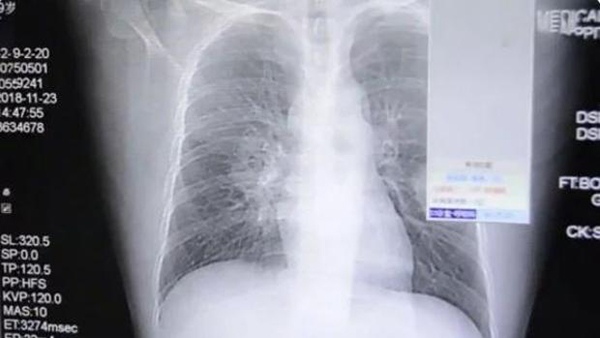

Peng, de 39 a?os de edad, fue en un primer momento a un hospital de Zhangzhou, provincia de Fujian, con tos y dolores en el pecho el 23 de noviembre. Los médicos pensaron que tenía una neumonía, pero a medida que iba empeorando y presentaba más dificultades para respirar le hicieron más pruebas, en las que le encontraron que lo que tenía eran hongos en el pulmón.

Fue entonces cuando Peng informó a los médicos de su extra?o hábito: disfrutaba oliéndose los calcetines después de un día de intenso trabajo. ?Todos los días, después del trabajo, olía los calcetines antes de lavarlos?, explicó a los medios locales uno de los médicos.

Los médicos dijeron que esa manía de oler los calcetines, unida a un sistema inmunitario débil y a la falta de sue?o —como consecuencia de su reciente paternidad— hizo que derivara en una infección pulmonar.